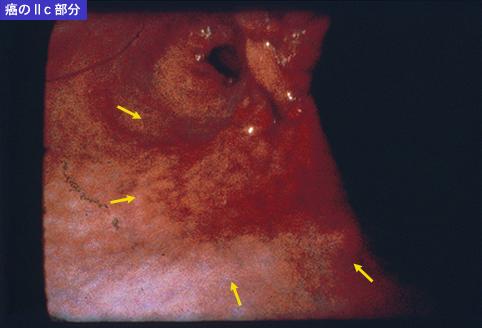

clasificación del pacienteTumor Epitelial Maligno/Cáncer a células en Sello de Anillo

parte(separada por órganos)estómago(región)/ángulo

método de exámenEndoscopia

clasificación ectoscópica de tumoresTipo 0(tipo superficial)/Tipo IIc(IIc+IIa)

diámetro mayor del tumor40 -

grado de penetraciónsm